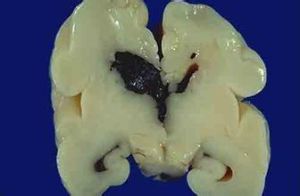

晚期腦內出血不是暴力直接作用的結果,而是由於外傷導致局部腦挫(裂)傷,或局部腦壞死軟化、水腫,致使局部血液循環紊亂、血管變性或炎症;或者暴力使腦內局部血管直接受損,病變繼續發展而使血管壁變性、壞死;或者腦內局部血管壁因損傷出血,形成假性動脈瘤。以後因某種原因,傷者血壓突然升高,已有病變的血管則破裂出血。其出血常呈大片狀,多發性,以大腦白質和基底節多見,亦易侵入腦室系統致腦室積血而死亡。因其出血部位與病理性腦內出血無特殊差別,所以有人稱這種出血為遲發性外傷後腦中風(delayed posttraumaticapoplexy)。

屍檢時除可見大腦白質和基底節部大片出血外,病理組織學檢查常能檢見彌散的血管壁變性、炎症、微小動脈瘤和軟化灶等病變。如能檢見陳舊性腦挫傷的改變,則有利於外傷性晚期腦內出血的鑑定。此外,死者可以是年輕人,有相應的頭部外傷史。有的外傷後晚期腦內出血見於手術清除腦內血腫後的一段時日。一般認為是使用脫水劑和由於血腫清除後,局部顱內壓突然降低,腦血流量增加,因填充作用而發生的出血。